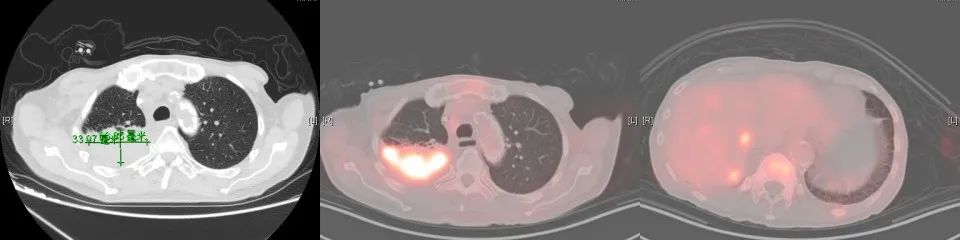

2017年7月行全身PET-CT提示右肺上叶高代谢病灶。2017年8月份行肺穿刺活检未能明确病理诊断。2017年10月份再次行全身PET-CT:右上肺结节增大,代谢增高,与家属商量后,外院予试用口服“吉非替尼”靶向治疗。

2018年1月复查胸部CT:右肺占位较前增大,余无明显特殊不适。外院再次行肺穿刺活检,病理:右肺组织见癌转移(符合膀胱癌肺转移)。2018年3月14-29日于我院行肺转移灶局部放疗。2018年5月15日-7月11日予标准方案化疗2周期。期间病情稳定。2018年10月复查,局部肺转移灶增大进展、且出现肺新转移灶,评估疗效PD,行NGS全基因检测,根据检测结果,即选用阿法替尼口服行靶向治疗。